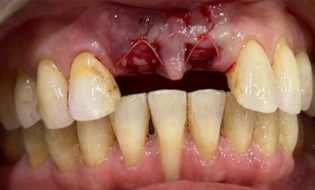

Figure 8

Figure 8 shows the patient just before the custom abutment was installed at the cementation appointment.

The patient broke the tooth in a game. At the time of the consultation, the tooth was barely hanging on by a thin sheet of buccal enamel so Dr. Kim suggested an extraction and an implant supported all ceramic crown.